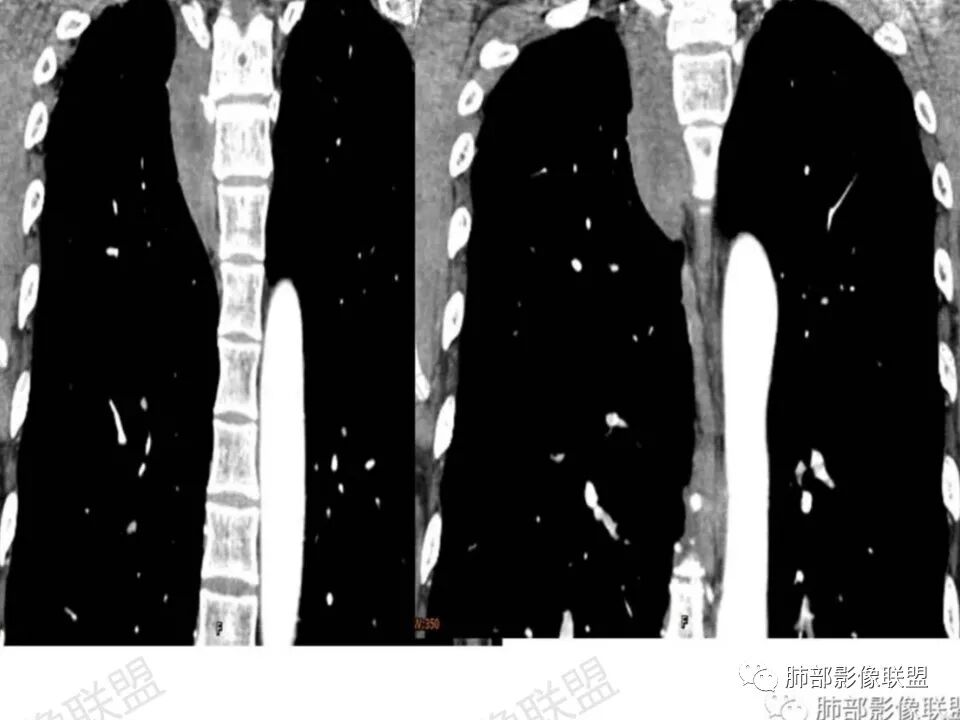

答:神经源性肿瘤的解剖位置及形态很重要—沿神经干方向生长走行。后纵膈内神经鞘瘤最常见的是神经根出入椎间孔处,并可沿着肋间神经方向分布,所以后纵膈神经鞘瘤通常横径大,上下径小,这个病例明显上下径长,所以不符合神经鞘瘤;神经节细胞瘤可沿着椎旁上下方向分布(参见上图黄色梭形的神经节),所以表现为上下径长,虽然生长方式符合,但是节细胞瘤以粘液为主,易钙化,该病例成分及强化方式不符合。